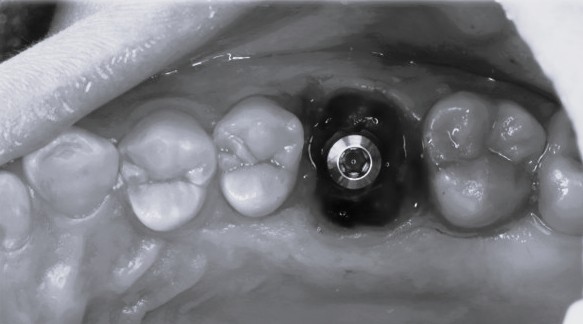

即時埋入での対応

上の奥歯は上顎洞までの距離が短くインプラントが難しいことも多いのですが、即時埋入用に開発されたインプラントを使えば抜歯と同時にインプラント埋め込みまで行うことができると判断しました。

約1時間で抜歯とインプラント埋め込みが終了しました。